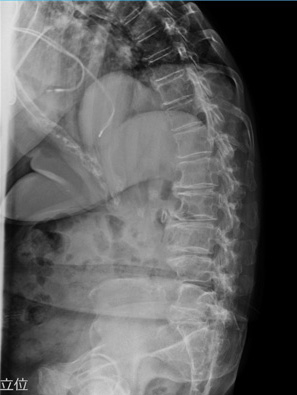

レントゲンで見る背骨の変化

腰痛の原因を調べる際には、単純レントゲン検査が行われることがあります。レントゲンでは骨の形や並び方を確認することができ、背骨の状態を客観的に見ることができます。

例えば、次のような変化が確認されることがあります。

レントゲン検査は短時間で行うことができ、腰痛の原因を探るための大切な手がかりとなります。ただし、腰痛の原因は筋肉や神経など骨以外にある場合もあるため、症状に応じて他の検査が行われることもあります。

腰痛の背景には、日常の姿勢や生活習慣が関係していることがあります。レントゲン検査では、背骨の並びや椎体の状態を確認することができ、腰痛の原因を調べる大切な手がかりになります。日頃から姿勢を意識し、適度な運動や休憩を取り入れながら、腰への負担を減らす生活を心がけましょう。気になる症状がある場合は早めに医療機関へご相談ください。